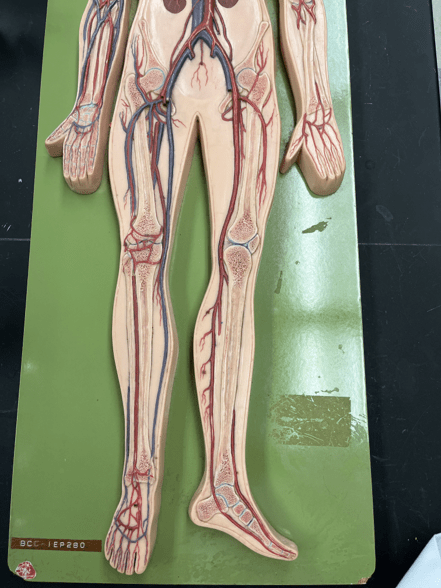

11

New cards

endothelium

• Part of the tunica interna.

• Composes a smooth inner surface of the vessel.

• Composes a smooth inner surface of the vessel.

12

New cards

valve

• Found in some veins.

• Establishes unidirectional flow of blood.

• Establishes unidirectional flow of blood.

13

New cards

common carotid artery

• An artery of the head and neck.

• Originates from the brachiocephalic trunk (R.) or the aortic arch (L.).

• Supplies the head and neck through its branches.

• Originates from the brachiocephalic trunk (R.) or the aortic arch (L.).

• Supplies the head and neck through its branches.